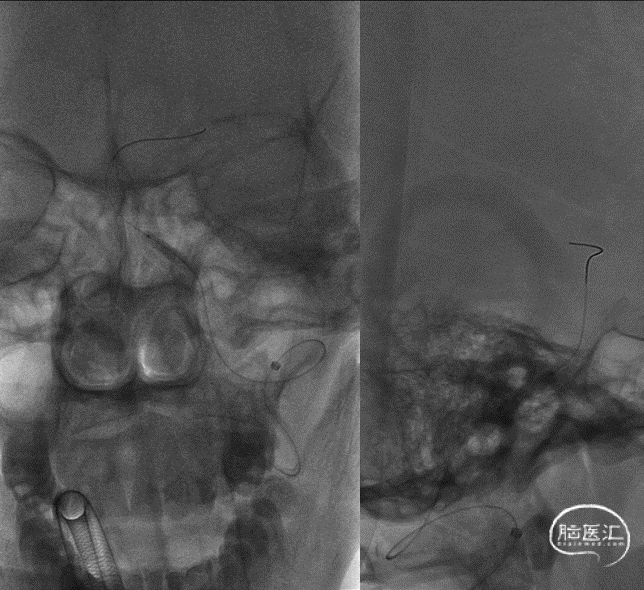

DSA(2022-01-19):

L-ICA

L-VA

R-ICA

复查DSA:左侧椎动脉V4段重度狭窄。

术前影像。

考虑到血管严重扭曲,以长鞘和6FNavien建立路径,微导丝、微导管通过病变。

微导管造影确认真腔。

球囊到位。

球囊扩张。

球囊扩张后狭窄有所改善。

支架顺利到达病变位置到位。

充盈球囊,释放支架。

支架释放后。